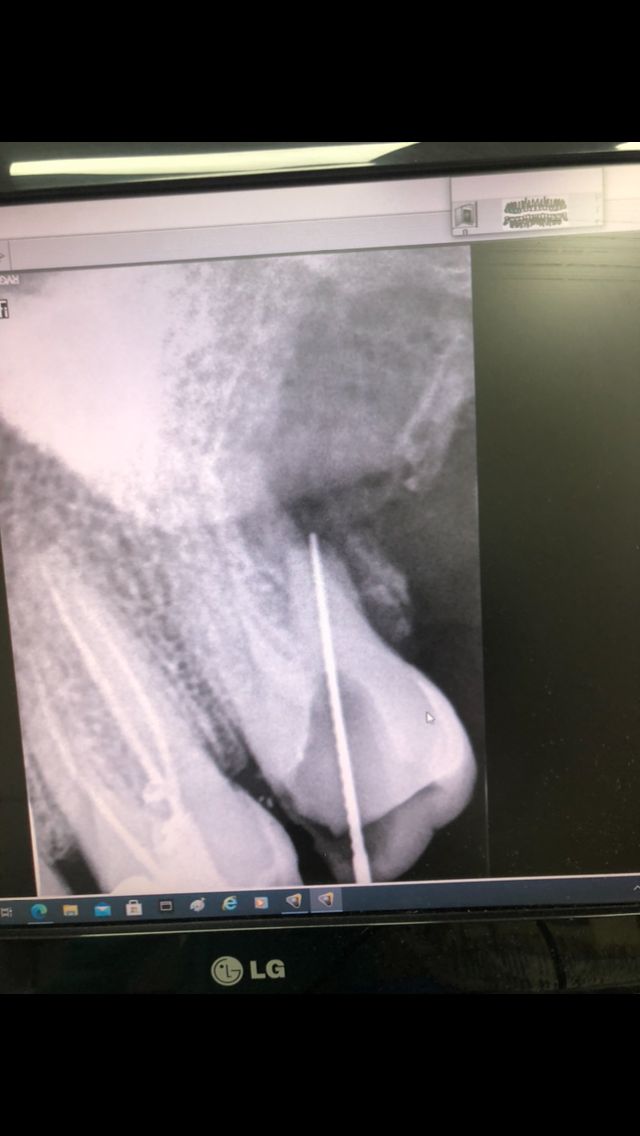

Al cabo de tres semanas con el paciente recuperado realizamos la segunda parte de la endodoncia: al hacer la conductometría vemos que la raíz distal vestibular sufrió una rizólisis por el impacto con el cordal. La rizólisis es una destrucción de la raíz de la pieza dental por impacto o presión de la cara oclusal de otra pieza.

Hacemos conductometría de la raíz vestibular mesial: